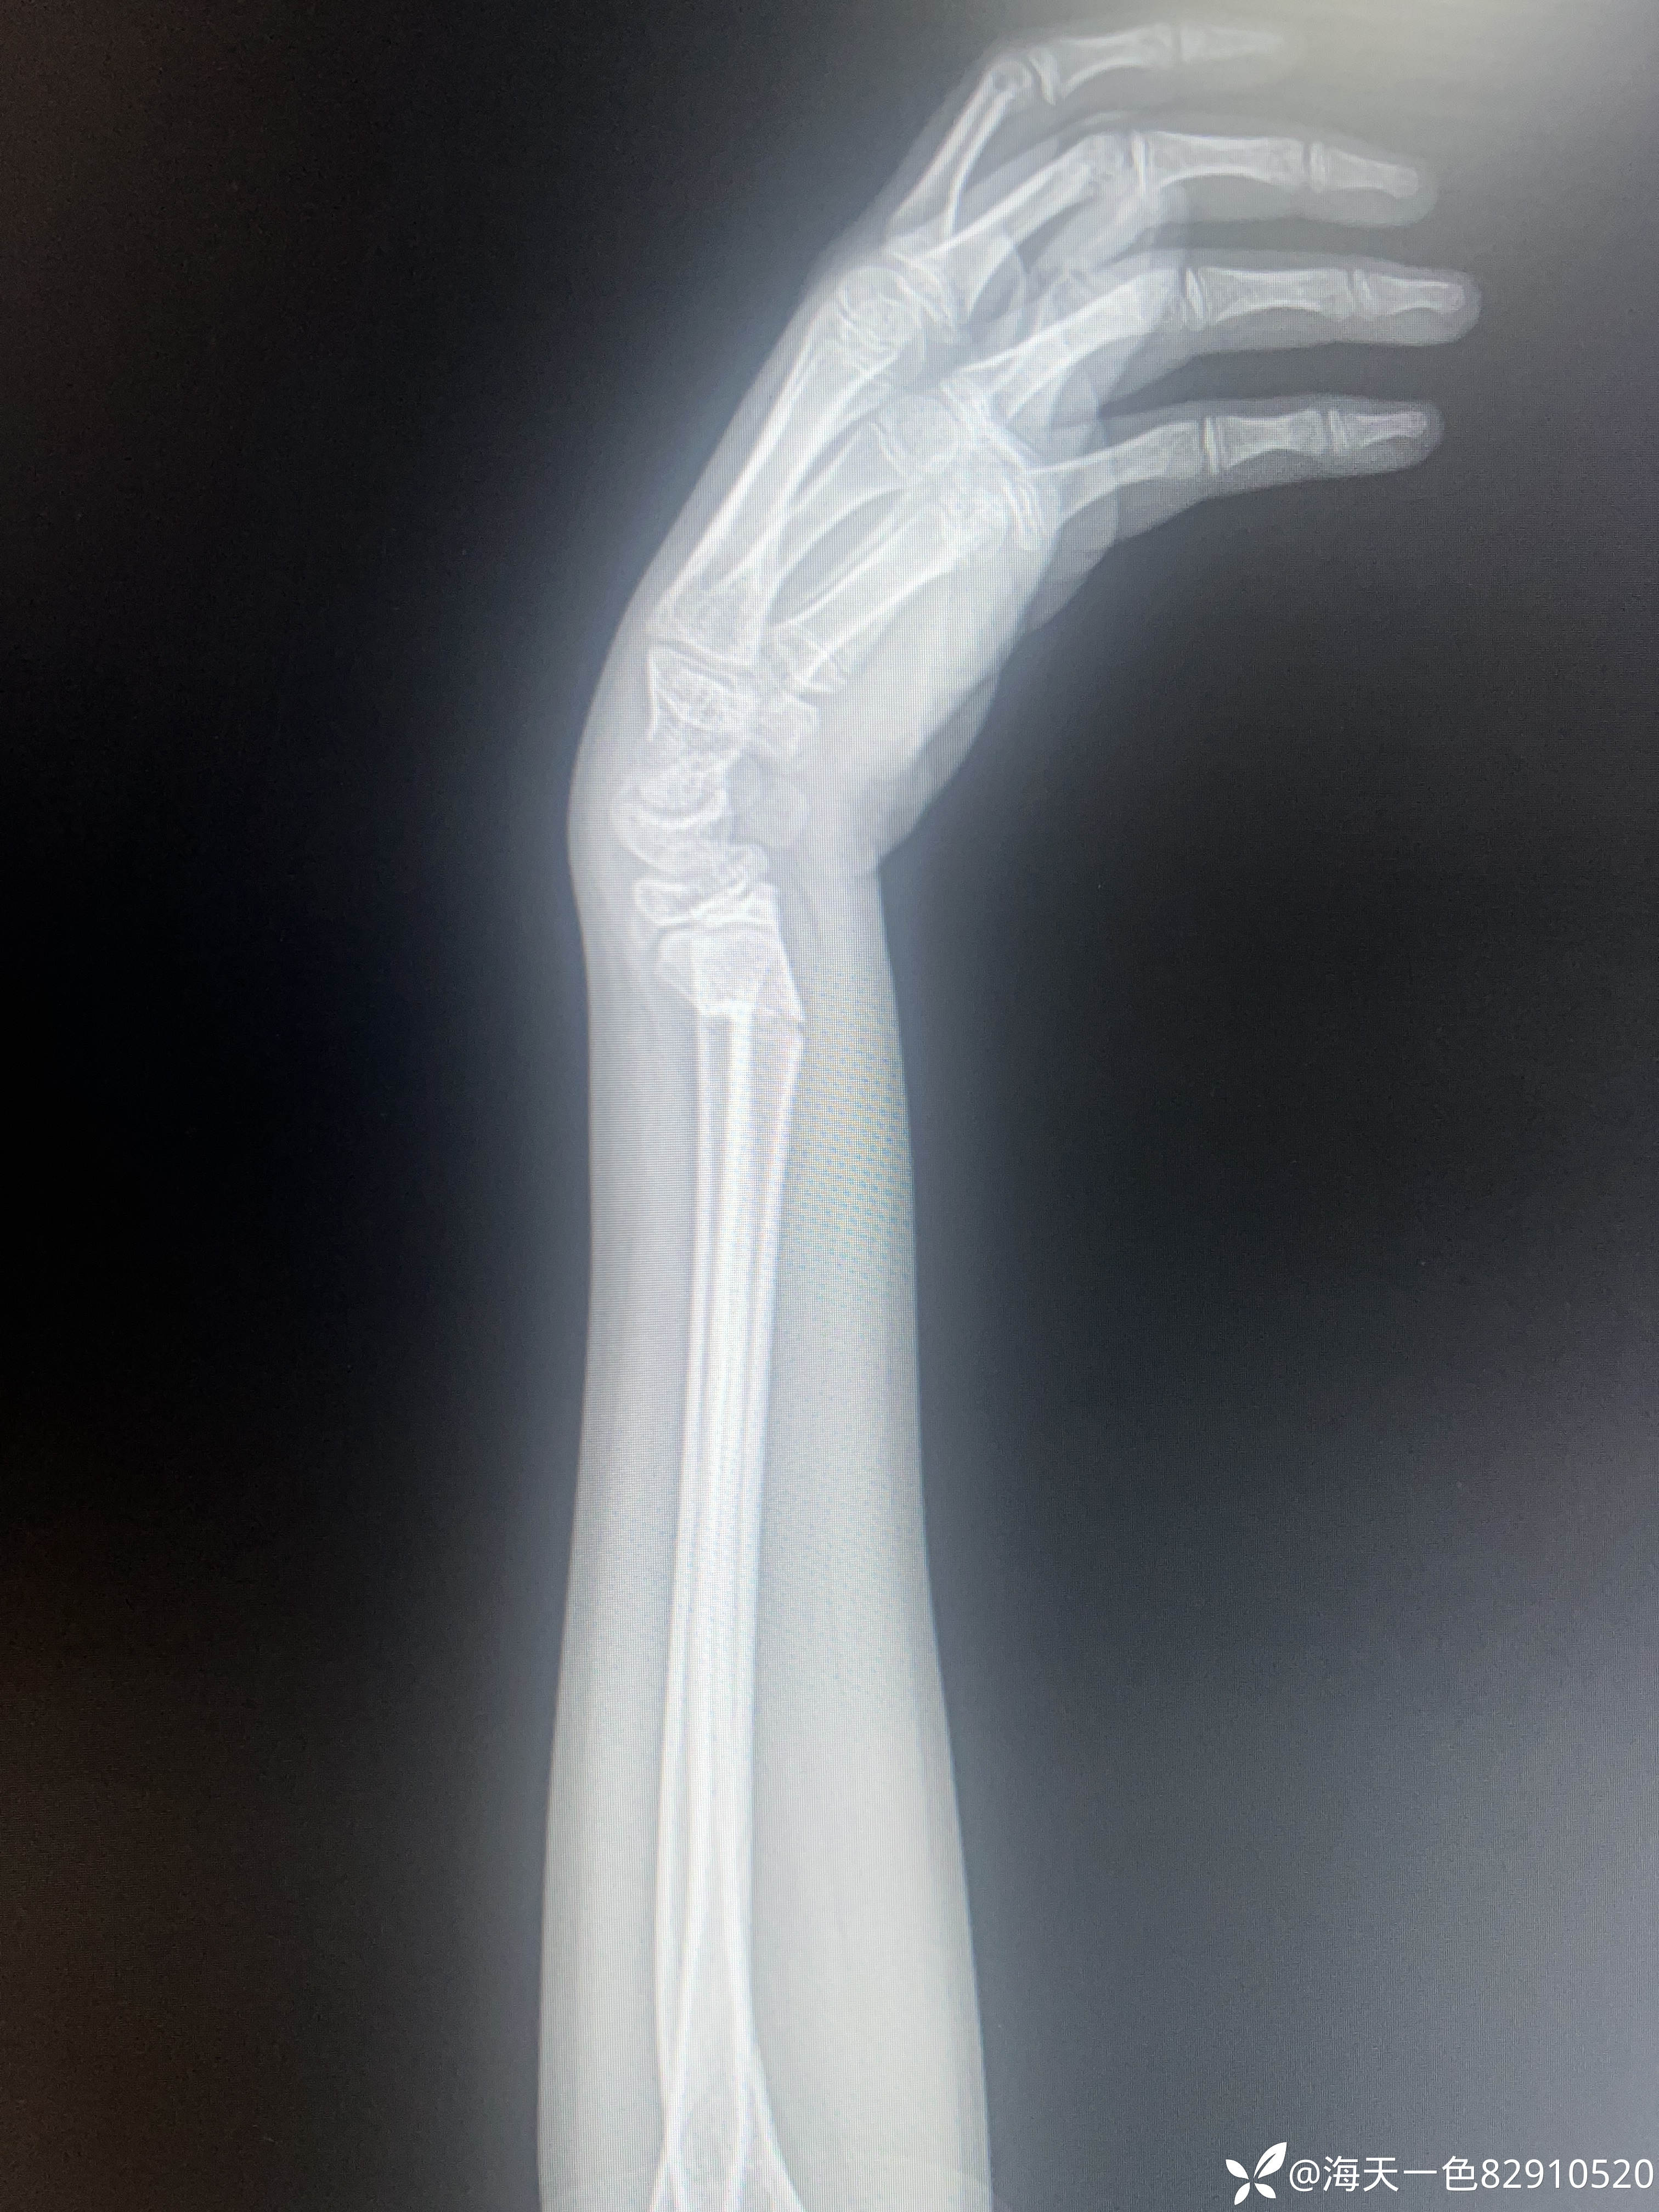

桡骨远端骨折

【患者信息】:患儿男性,14岁,

【主诉】:跑跳时不慎摔伤左腕关节肿痛14天

【临床诊断】:左桡骨远端骨折

【治疗经过及结果】:建议手术手术治疗,患儿家属未手术治疗,外院进行手法复位,复位拍片如下